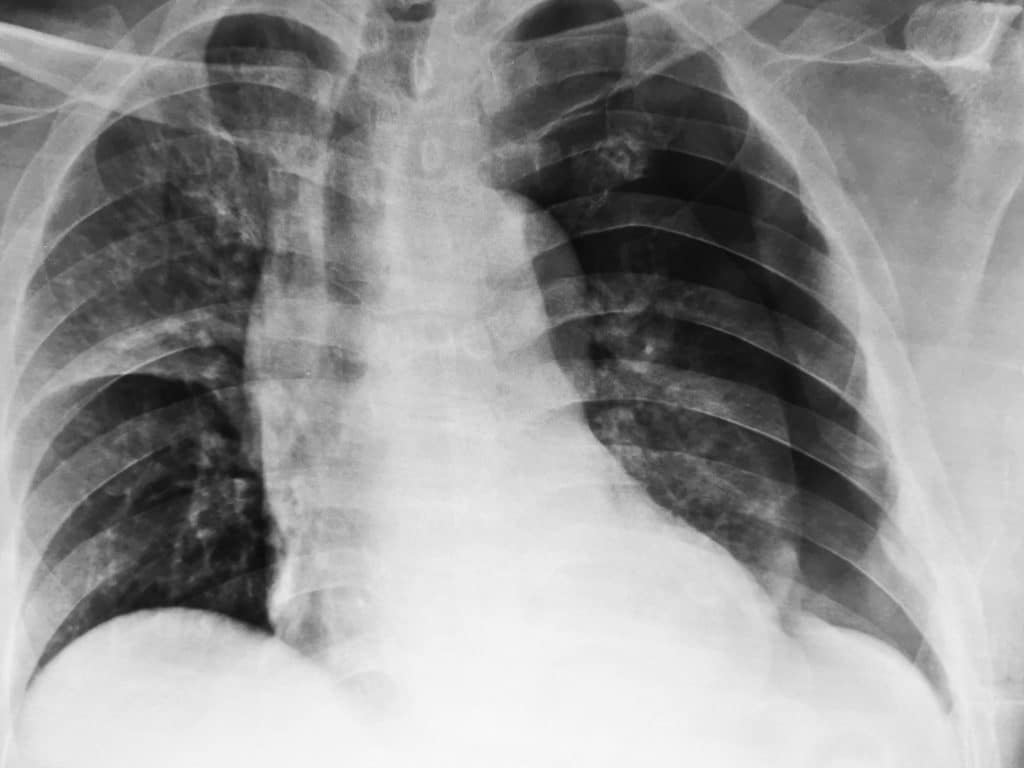

Chest radiographic images of the pneumothorax. Chest radiograph How To Diagnose Pneumothorax On Chest X Ray Pneumothorax should be suspected in patients who present with acute dyspnea and chest pain (classically pleuritic), particularly in those. Recognition of a pneumothorax depends on the volume of air in the pleural space and the position of the body. In some cases, a computerized tomography (ct) scan may be needed to provide. How To Diagnose Pneumothorax On Chest X Ray.

Xray of the Chest of a Man with a Pneumothorax Stock Image Image of How To Diagnose Pneumothorax On Chest X Ray Recognition of a pneumothorax depends on the volume of air in the pleural space and the position of the body. In some cases, a computerized tomography (ct) scan may be needed to provide. Pneumothorax should be suspected in patients who present with acute dyspnea and chest pain (classically pleuritic), particularly in those. How To Diagnose Pneumothorax On Chest X Ray.